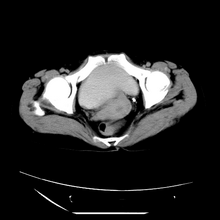

女性,41岁,发现左腹部包块3年,现行ct检查,检查前做过静脉肾盂造影。

左侧低密度区是脂肪密度,中间可见条索状软组织样密度影,现主要想知道左肾前下缘圆形软组织样密度影,内见低密度水样密度影,这是什么?

脾脏增大,左肾后方脂肪增多,脊柱前方脂肪增多,左肾窦脂肪增多,左肾变形,双肾积水以左侧为著,左肾内侧及上方见环形软组织肿物影,内部低密度区,考虑1盆腹腔/腹膜后及左肾窦脂肪增多症2左肾内侧病灶可能为左肾上腺病灶,可能为脂肪增多的原凶

1)考虑左肾替代性脂肪瘤病;不排除左肾错构瘤。2)双肾积水。

左肾周脂肪堆积征【原因?】,双肾逆行造影术后;脾大【原因?】

1、考虑左肾替代性脂肪瘤病,2、双肾积水,3、距脾,4、楼主说的我考虑为感染性病灶。

腹膜后脂肪肉瘤累及左输尿管及左肾窦脂肪沉积,双肾积水,